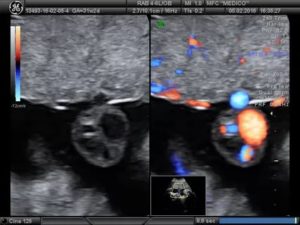

При этом, эхографически подобные аномалии являются анэхогенными образованиями, которые находятся в структуре пуповины, при этом, не нанося вреда ходу кровеносных сосудов.

- Допплерометрия, которая заключается в проведении исследования кровотока пуповины;

При ультразвуковом обследовании кисты заметны. Они никак не влияют на кровообращение между плодом и плацентой.

Кисты пуповины встречаются примерно в 3% беременностей. Существуют истинные и ложные кисты. Истинные кисты выстланы клетками и обычно содержат остатки ранних эмбриональных структур. Ложные кисты являются заполненными жидкостью мешочками, которые могут быть связаны с отеком желе Уортона.